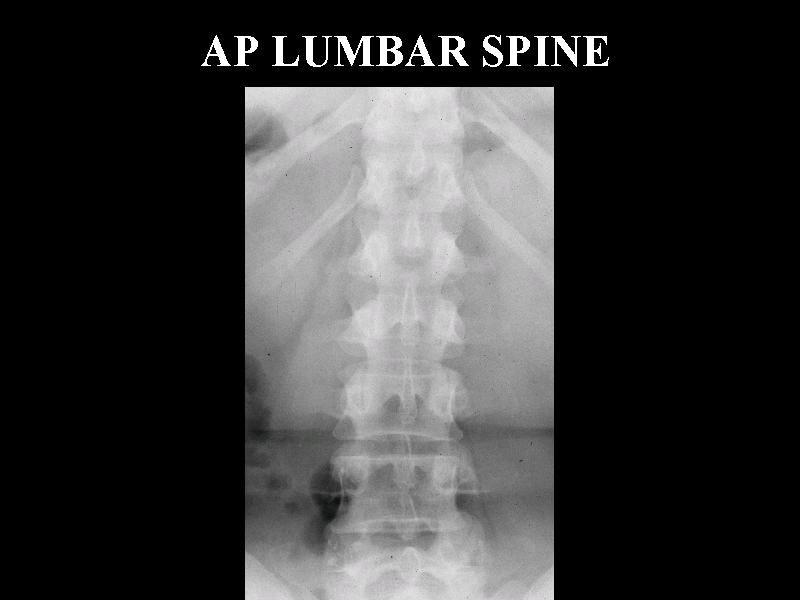

MS 185 NL AP LS